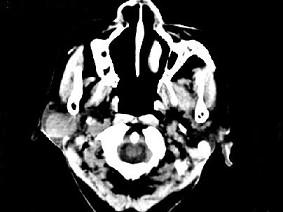

问题 女,72岁,六年前于右面颊部扪及一包块,缓慢增大,其表面较光滑,CT如图所示,该病例应诊断为 ( )

选项 A、颈部淋巴瘤 B、小唾液腺瘤 C、腮腺混合瘤 D、颈部神经纤维瘤 E、Worthin瘤

答案 C